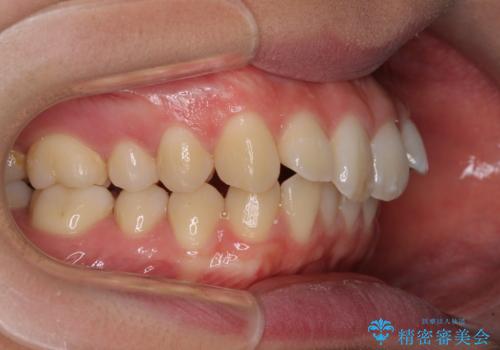

上下歯列の前後位置を見ると、上顎が全体的に前方に位置しており、上顎前歯が前方に突出しているものの、横顔の印象はそれほど口元が突出しているものではない状態でした。

上下の抜歯位置を変えることで、左右ともに理想的な咬み合わせを達成することができました。

横顔の印象はほとんど変わらないものの、唇を閉じたときに前に出ていた下唇が、治療後には少し下がった状態に仕上げることができました。